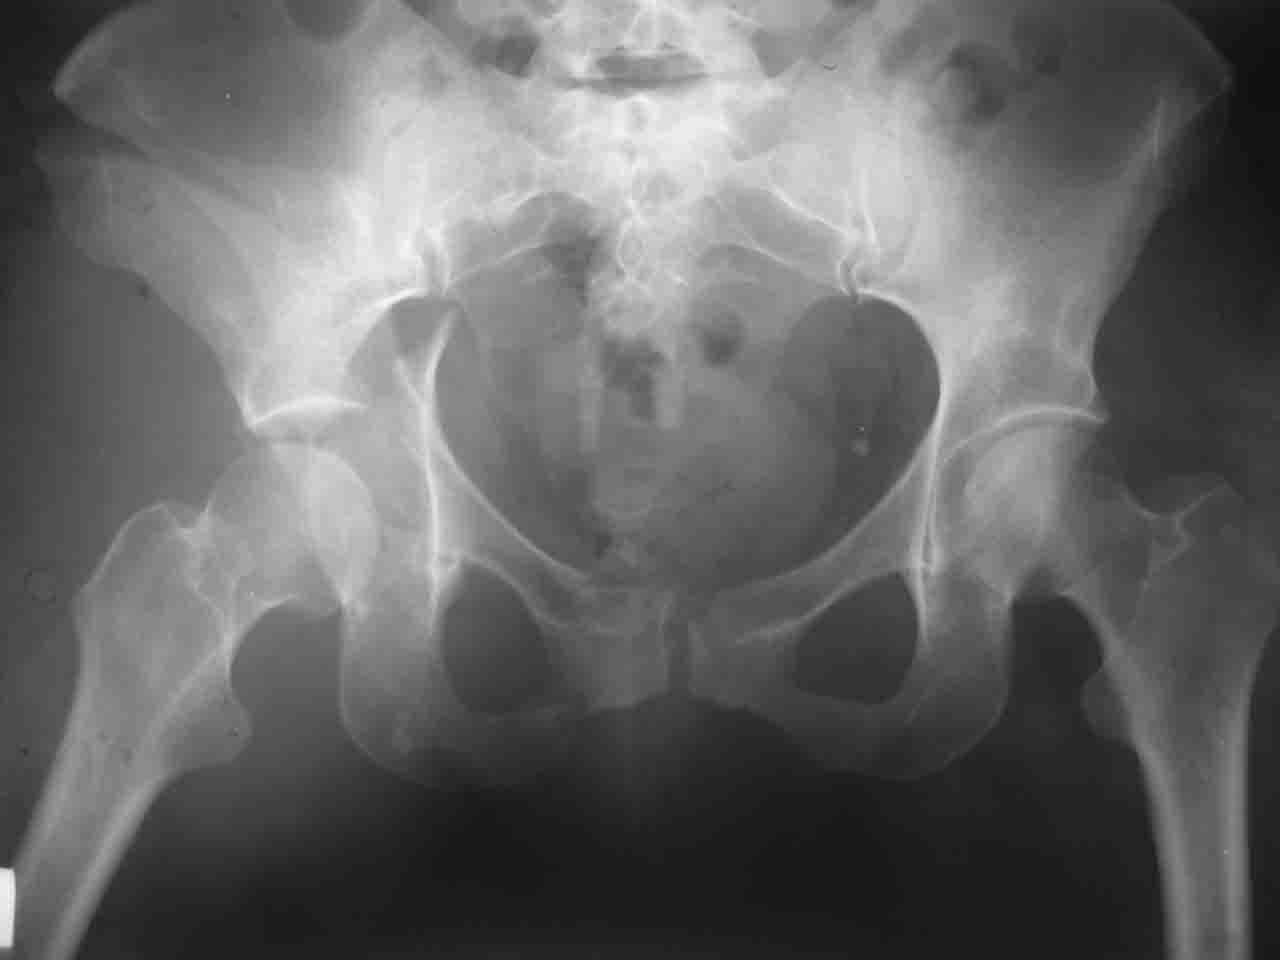

Спасибо за комментарии и рекомендации. Откровенно говоря, больного я прооперировал на прошлой неделе, через 5 дней после аварии и проблем с ним пока никаких нет, на удивление при достаточно обширной диссекции (илиофеморальный доступ) болей практически нет, так что больной самостоятельно садится в кровати, выполняет активные движения в оперированном суставе, сгибая до 60 градусов пока, далее с ассистенцией.

Причиной обращения к сообществу были возникшие непосредственно после операции сомнения и разочарования полученным качеством репозиции: а надо ли было трогать перелом вообще, репозиция передней колонны технически была очень сложна для меня, хотя реконструкции была в той же последовательности, что Д-р А.В.Рунков рекомендовал, в какой-то момент безуспешных манипуляций стал думать о *вторичной конгруэнтности*, которую не так давно обсуждали на

форуме и скелетном вытяжении. С репозицией и фиксацией задней колонны и отдельно задне-верхней стенки впадины проблем не возникло. Послеоп. Рг граммы в приложении. Если возникнут какие-либо дополнения или поправки - был бы признателен.